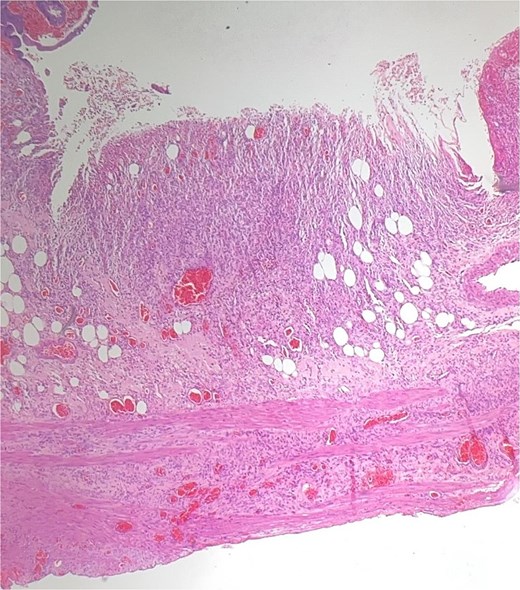

Histological evaluation confirmed acute necrotizing colitis with transmural inflammation and granulation tissue (Figs 4 and 5). Hepatic cyst biopsies revealed benign biliary duct cysts with cystically dilated bile ductules.

Histopathology: complete surface ulceration with granulation tissue (H&E, × 40).